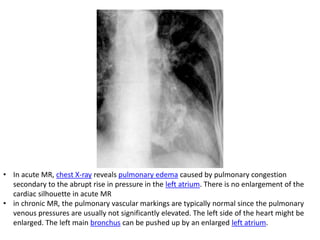

• In acute MR, chest X-ray reveals pulmonary edema caused by pulmonary congestion

secondary to the abrupt rise in pressure in the left atrium. There is no enlargement of the

cardiac silhouette in acute MR

• in chronic MR, the pulmonary vascular markings are typically normal since the pulmonary

venous pressures are usually not significantly elevated. The left side of the heart might be

enlarged. The left main bronchus can be pushed up by an enlarged left atrium.